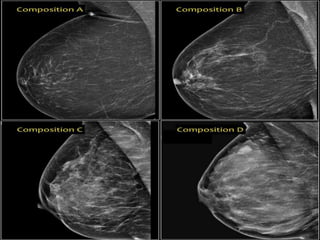

• In the BI-RADS edition 2013 the assignment of the breast

composition is changed into a, b, c and d-categories followed

by a description:

• a- The breast are almost entirely fatty.

Mammography is highly sensitive in this setting.

• b- There are scattered areas of fibroglandular density.

The term density describes the degree of x-ray attenuation of

breast tissue but not discrete mammographic findings.

• c- The breasts are heterogeneously dense, which may obscure

small masses.

Some areas in the breasts are sufficiently dense to obscure

• d- The breasts are extremely dense, which lowers the

sensitivity of mammography.